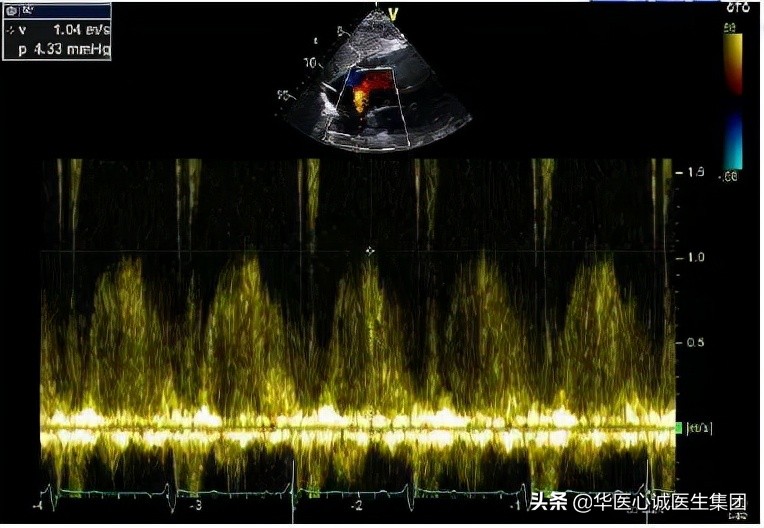

房间隔缺损

该患者还存在房间隔缺损,但缺损面积不大。如果没有其他问题,该患者可能不会出现症状。

但因为有高血压、左心衰、左室肥厚等,左室压力升高后,左房压升高,是否会造成分流量更大?由此可以看出,超声可以清晰的显示病理生理的改变、血流动力学的异常等,这就是超声的魅力所在。

该患者房缺面积不大,但因为左房压高,导致房缺的分流量很大,所以右心明显扩大。